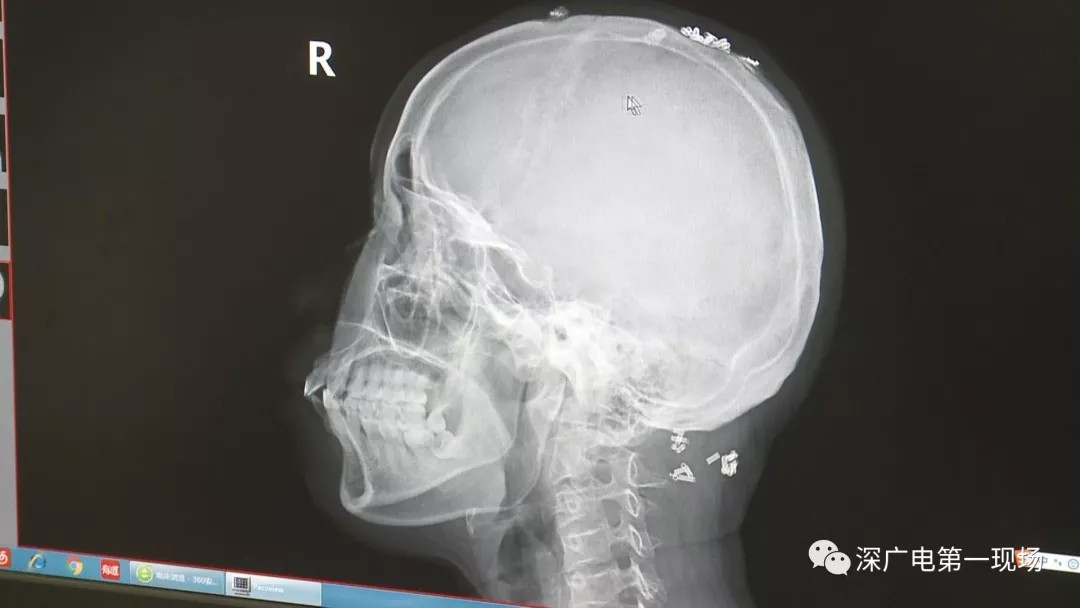

從X光影像圖片中可以看到

患者周身布滿了彈簧圈

深圳大學總醫(yī)院神經(jīng)外科副主任醫(yī)師陳富勇介紹,當時檢查的時候發(fā)現(xiàn),該患者從頭部到腿部,基本上每個地方都有彈簧,很難數(shù)清具體數(shù)目。